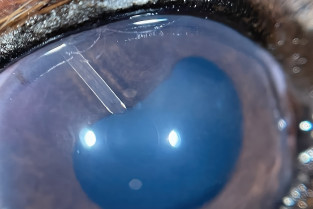

Connaître et appliquer les techniques actuelles dans la chirurgie du globe.

Connaître et appliquer les techniques actuelles dans la chirurgie de greffes cornéennes.

Connaître et appliquer les techniques actuelles dans la chirurgie du glaucome.

Connaître et appliquer les techniques actuelles dans la chirurgie du segment postérieur.